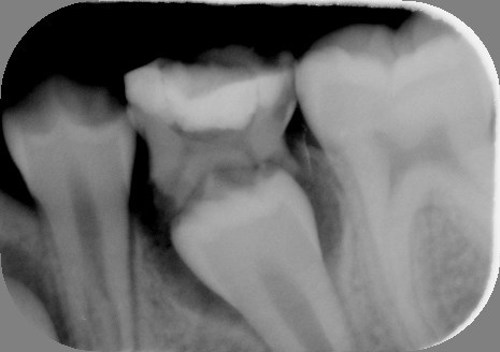

I kæben under mælketænderne ligger de nye blivende tænder, som er under udvikling. Mælketændernes rødder bliver opløst, efterhånden som de nye tænder vokser. Til sidst falder mælketanden ud, når hele tandens rod er væk.

På første røntgenbillede er den blivende tand ved at skubbe mælketanden ud. På det andet er mælketanden lige ved at falde ud.